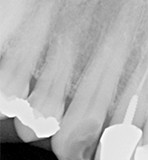

A digital periapical X-ray (PA) (Fig. 12) was taken using Air Techniques ScanX phosphor plates. The PA revealed caries into the pulp. The tooth would require endodontic therapy, a post core and a crown.

Fig. 12 Fig. 13

Root canal therapy was completed (Fig. 13).